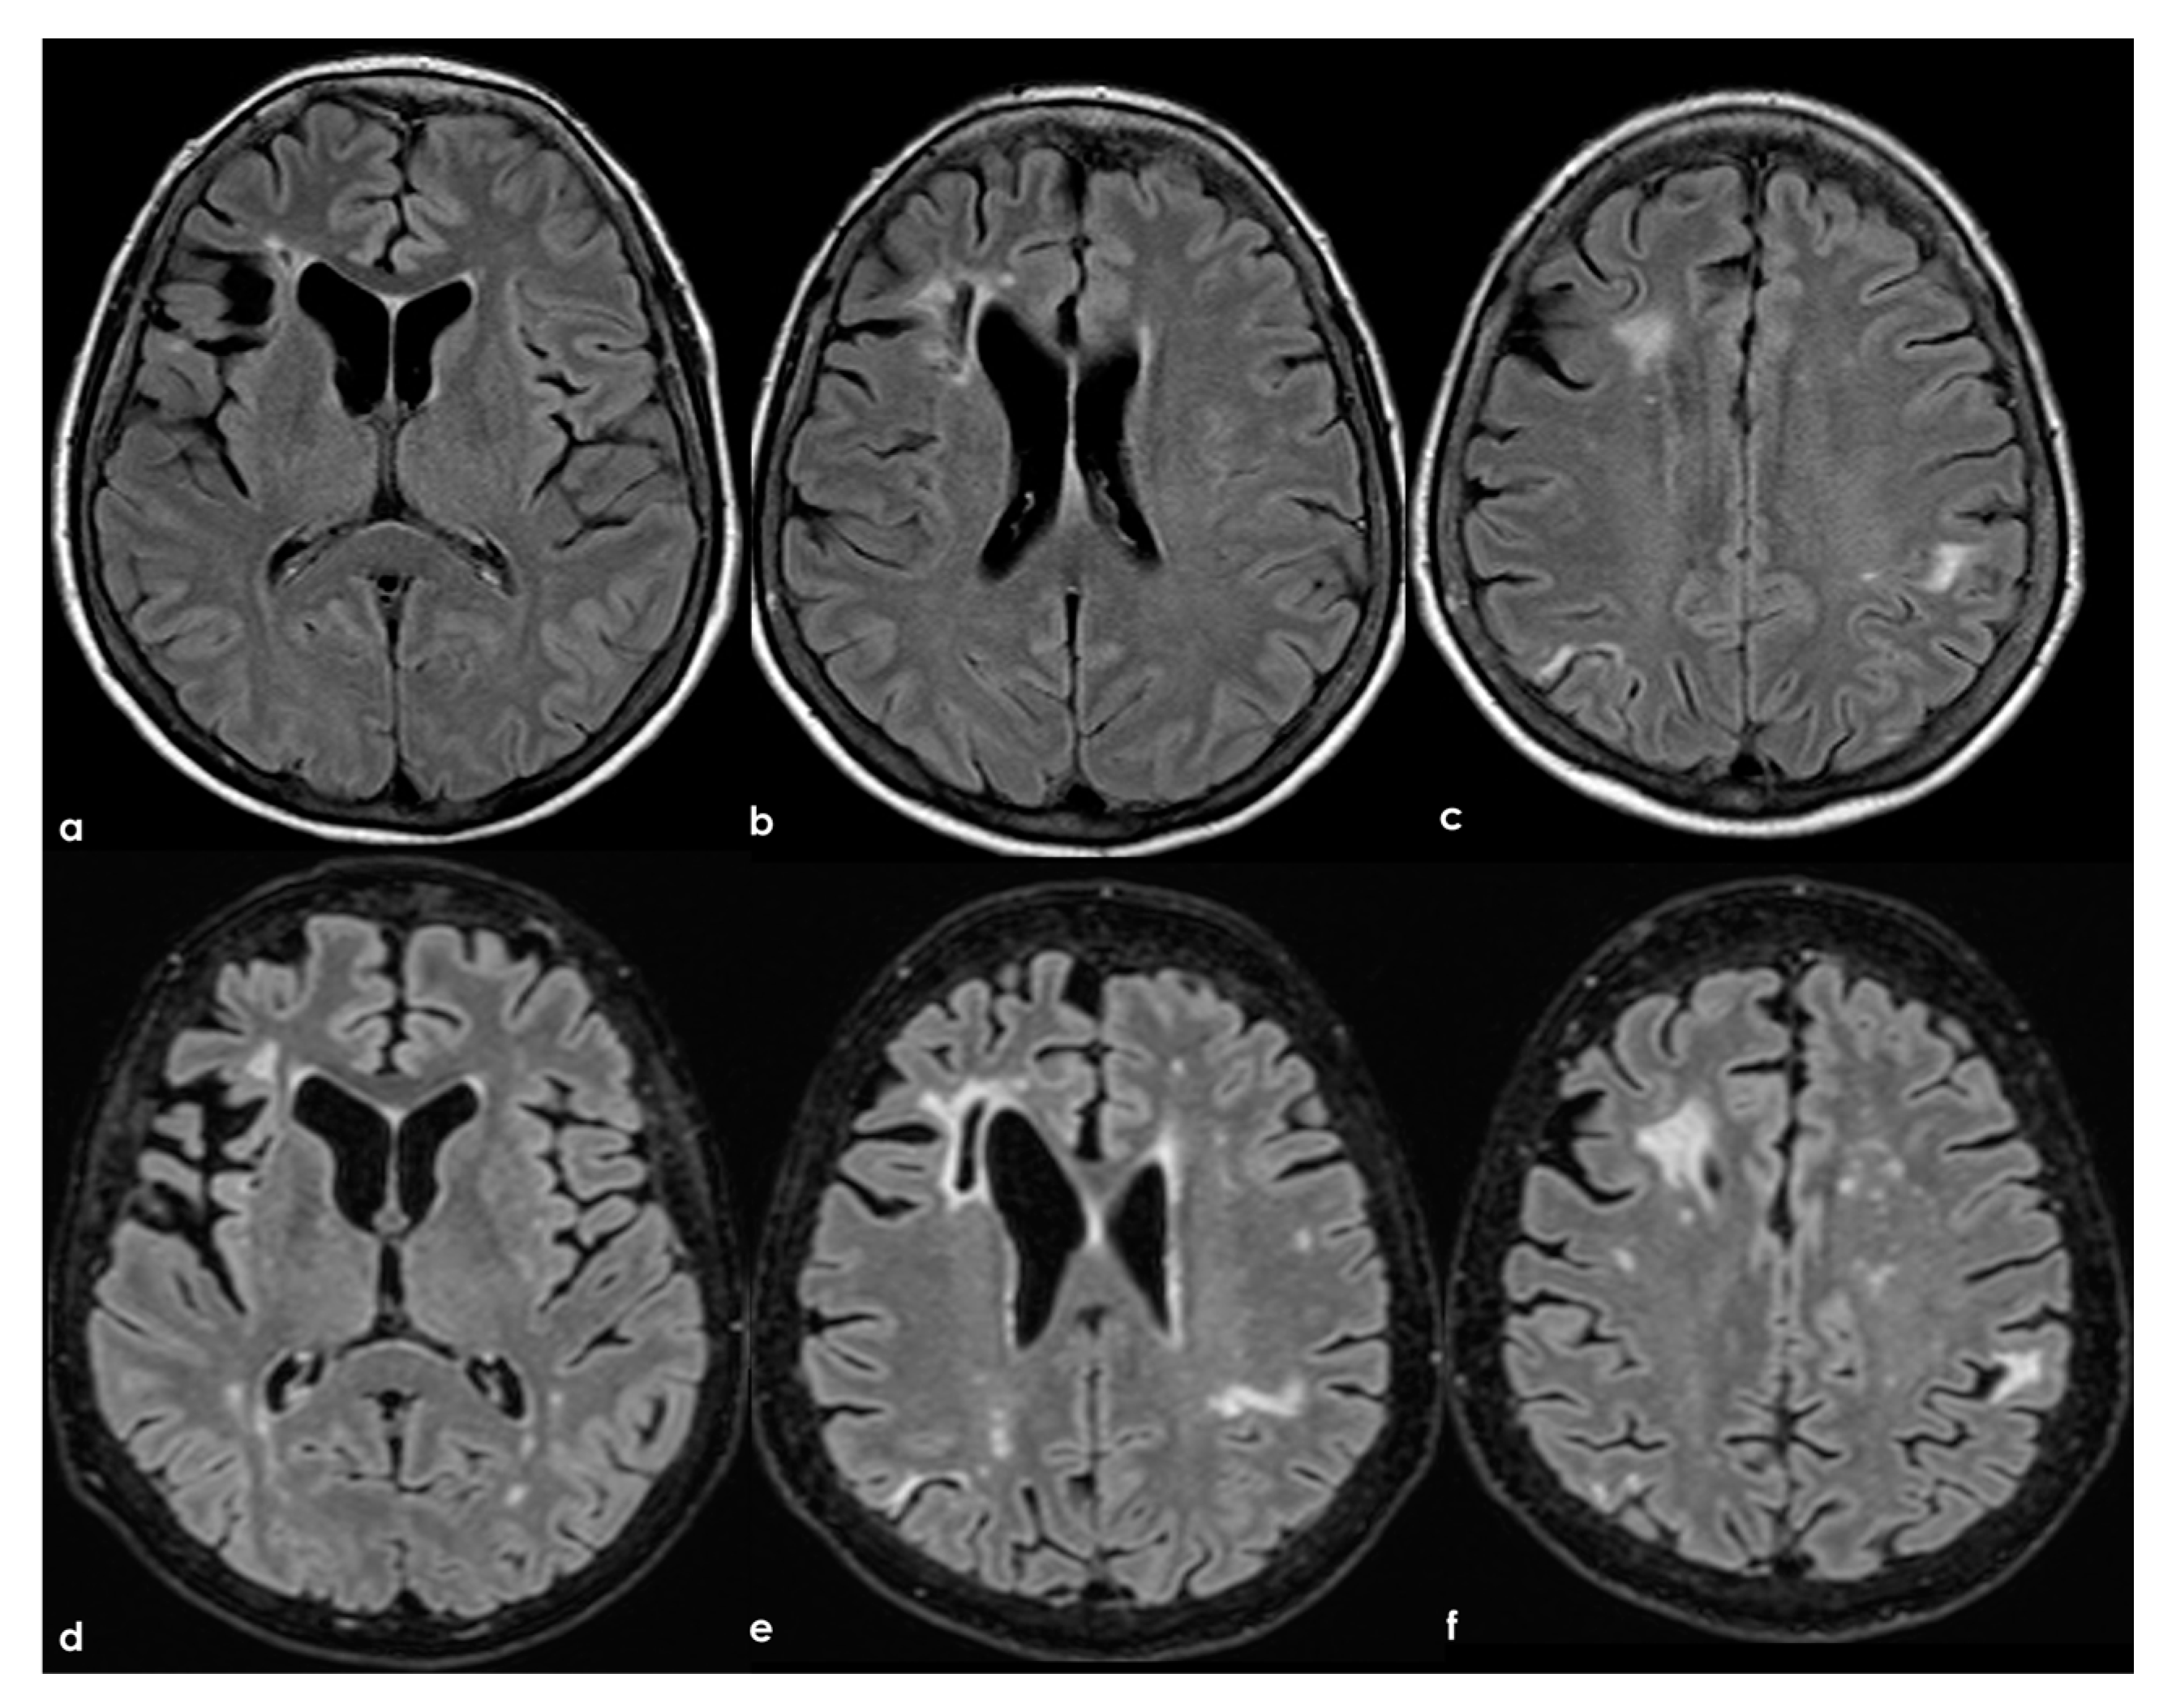

To date, as summarized by Hassan F et al. [], most studies investigating cognitive impairment in individuals carrying aPL and in those with APS have been limited by small sample sizes and significant variations in cognitive-impairment detection methods, the specific aspects of cognition assessed, and the types of antibodies examined (e.g., aCL, LA, or aβ2GPI), as well as the laboratory cutoffs used to define positivity []. In general, aPL carriers represent a highly heterogeneous group with substantial variability in the prognosis and risk of cognitive impairment. The absence of standardized methods for quantifying aPL, which may also change over time, and fluctuations in cutoff levels for positivity, pose challenges in comparing findings across different studies. APS can be secondary to autoimmune diseases, which can independently affect the CNS and contribute to cognitive impairment. Moreover, aPL antibodies are more commonly detected in the elderly population, among whom cognitive impairment and dementia are prevalent []. Consequently, the precise frequency and mechanisms of cognitive impairment in APS, their correlation with aPL activity, and the optimal approaches to diagnosis and treatment remain uncertain []. In fact, in a recent systematic review [] aiming to investigate the association between APS and cognitive dysfunction, the authors concluded that studies including neuroimaging biomarkers in APS/aPL-positive patients with cognitive dysfunction were scarce and heterogeneous; thus, multicenter studies with standardized image acquisition and international APS clinical and laboratory criteria are required. In Figure 2, an example of mild SVD involvement in a patient with APS (triple positivity) is proposed.

Figure 2.

Brain MRI (axial FLAIR in panels (a–d), coronal T2W in panels (a–g), and axial T2W in panel (h)) showing small punctate white-matter hyperintensities in the centrum semiovale, with a trend to watershed distribution (panel (d)), and a mild increase in enlarged perivascular spaces in the subcortical white matter (panels (e–h)).

In the longitudinal evolution of neuroradiological patterns, SVD markers might appear, as in Figure 8 (same patient as in Figure 7 but 8 years later and without new clinical events on anticoagulant treatment).

Figure 8.

Brain MRI (axial FLAIR) at baseline (panels (a–c)) and after 8 years (panels (d-f)), showing the increase of WMHs in the subcortical white matter.